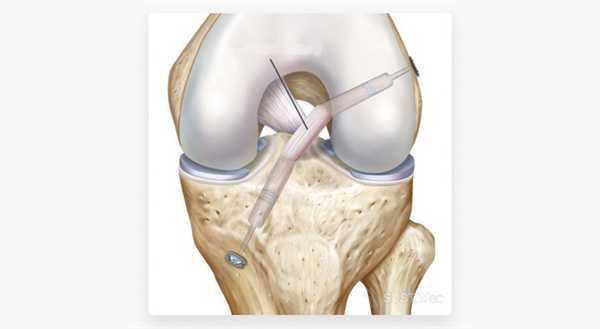

Современная медицина предлагает несколько способов проведения оперативных вмешательств при привычном вывихе надколенника. Оптимальная методика — артроскопическая реконструкция (пластика) медиальной пателлофеморальной связки (МПФС). С помощью данного метода операция при вывихе надколенника позволяет восстановить утраченную анатомическую структуру, стабилизирующую надколенник (МПФС), и одновременно зашлифовать и резецировать участки поврежденного хряща без больших кожных разрезов.

Как проводится артроскопическая реконструкция?

Сначала под контролем эновидеокамеры совершаются два прокола. Они позволяют провести визуальный осмотр всех отделов сустава, при необходимости хирургически обработать поврежденные участки хряща. Затем, через два новых прокола, проводится и фиксируется сухожильный трансплантат, заменяющий утраченную поддерживающую связку надколенника. Натяжение связки регулируется под контролем видеокамеры так, чтобы вывести надколенник из положения подвывиха, но оставить физиологически достаточную свободу его смещения.